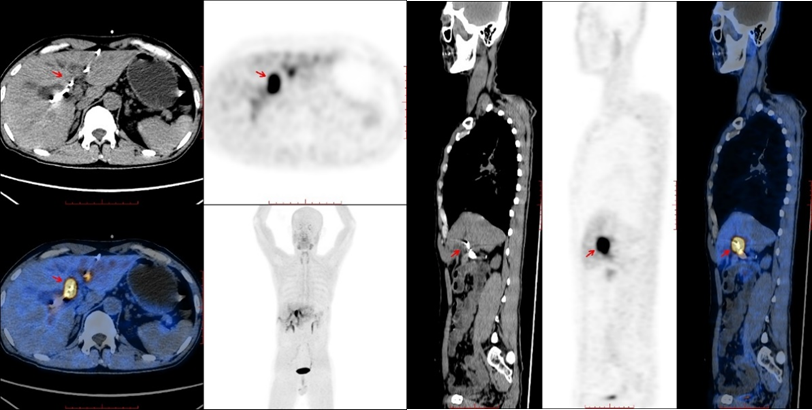

2021年9月,PET-CT显示肝门部病灶(见图1)。

图1 PET-CT结果